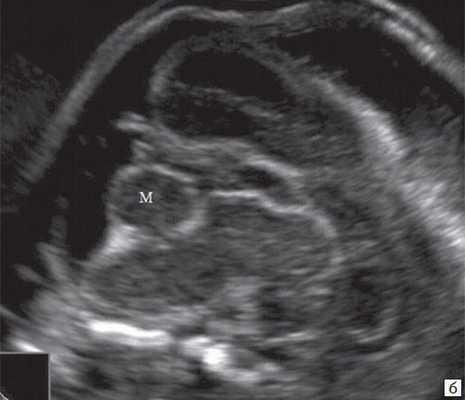

При частичном РЭС в наблюдении 4 картины желудочковой системы (затылочные рога боковых желудочков - 7 и 7,9 мм, 3-й желудочек - до 2 мм), комплекса "полость прозрачной перегородки (ППП - 3,4 мм) - мозолистое тело (20,8 мм)", борозд мозга (глубина сильвиевой борозды - 7 мм), длины крыши четверохолмия (8,3 мм), водопровода, передне-задних диаметров мезенцефалона (11 мм) и моста (7,9 мм) соответствовали норме (рис. 6).

На эхограмме: М - мозжечок, Ц - цистерна, стрелка короткая - намет мозжечка, стрелка длинная - 4-й желудочек.